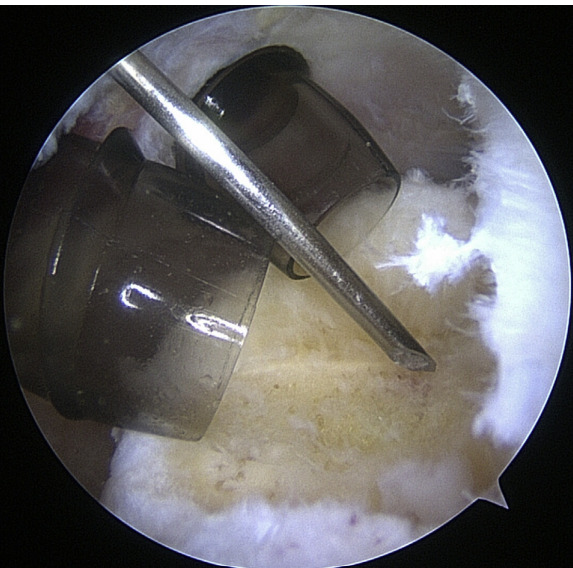

Arthroscopic shoulder surgeries are among the most common minimally invasive procedures (MIS) used to restore shoulder function. Shoulder arthroscopy and arthroscopic rotator cuff repair rates, broken down by geographic location, ranged from 64.96 to 623.6 per 100,000 persons in more recent research.23 The most frequent orthopedic operation for partial meniscectomy is knee arthroscopy, followed by shoulder arthroscopy. Shoulder arthroscopy is a common method for treating pathologic shoulder conditions including adhesive capelusitis, subacromial impingement, illnesses affecting the proximal biceps, rotator cuff tears, labral tears, loose bodies, and degenerative arthritis. Management of shoulder instability and rotator cuff pathology are the two most prevalent reasons for arthroscopic shoulder surgery. There are many advantages of arthroscopy over open surgery. Some of them include a better ability to see intra-articular disease, less complications, shorter recovery times, and less time away from work.6

Instrumentation

When it comes to shoulder arthroscopy, the most common arthroscope utilized is the 4.0 mm 30 scope. A 30-magnification scope is sufficient for most situations. An arthroscopic-assisted coracoclavicular reconstruction, subscapularis repairs, Remplissage procedures, glenohumeral ligament lesions, and humeral avulsion can all benefit from the use of a 4.0-mm 70 arthroscope, which should always be on hand. There should be a large selection of cannulas accessible, and they will differ according on the operation being carried out.25

As the principal penetrating instruments, 5.5-mm blunt-tipped cannulas are often used for portal insertion. Blunt tips are preferred to reduce the likelihood of iatrogenic harm, especially to articular cartilage. Because they are easily passable by the majority of arthroscopy passing devices, 8.25-mm cannulas are often employed for “instrumentation” portals. In addition, cannulas of 6.5 mm or less are commonly used in suture management. Cannulas that are threaded or have locking mechanisms are preferable since they are less likely to come free from the joint. In most cases, one of two methods can be employed: gravity or a pump system. Sufficient management of pressures, usually approximately 60 mm Hg, is necessary to avoid significant soft-tissue edema, which can complicate the use of cannulas and instruments.25

Setup

The coracoid, acromioclavicular joint, clavicle, and acromion are all marked on the skin. If subacromial work is going to be performed, the subacromial bursa may be infiltrated with up to 30 cm3 of a mixture of 0.25% bupivacaine and epinephrine. A standard posterior portal is the typical site of access to the subacromial area and glenohumeral joint. The typical placement of this opening is 2 centimeters medial and 2 centimeters distal to the posterolateral border of the acromion. Palpating the soft tissues of the posterior glenohumeral joint is a common way to confirm the proper position. An anterior portal develops after the joint has been inserted. Figure 4 shows that the surgeon has the option of employing a spinal needle to perform it from the outside in or an inside out approach, depending on his or her choice. The anterosuperior portal is located just off the outside edge of the acromion. You may find the anteroinferior portal directly on the side of the coracoid. One centimeter below the anteroinferior portal is the 5 o’clock portal, which is defined as passing through the subscapularis tendon. Scientists say this entry point is the most common and least invasive as it mimics neurovascular systems. Any anterior portal may be used to conduct basic shoulder arthroscopy. Figure 5 shows the setup of both anterior portals for biceps tenodesis, subscapularis repairs, and labral repairs. For posterior labral repairs, spinal needle localization allows for the creation of an auxiliary posterolateral portal situated immediately distal to the posterolateral limit of the acromion. Anterior positioning of the Wilmington portal, one centimeter laterally to the posterolateral margin of the acromion, is recommended for superior labral repairs. The posterolateral and Wilmington portals are types of trans-rotator cuff tendon access points. Cannulas with the smallest diameters necessary should be used.25

The subacromial region may be accessed via the posterior portal if needed after any intra-articular procedures are finished. Spinal needle localization allows for the creation of a lateral portal, typically 2 cm laterally to the acromion’s lateral border and aligned with the clavicle’s posterior border (Figure 6). For any subacromial surgery, pre-positioned anterior portals may be used (Figure 7). An extra Neviaser portal may be made underneath the spinal needle localization, precisely below the acromioclavicular joint, if that becomes essential. This may be useful for a variety of suture procedures, including those involving the superior labrum, the rotator cuff, and the decompression of the suprascapular nerve (Figure 8).25